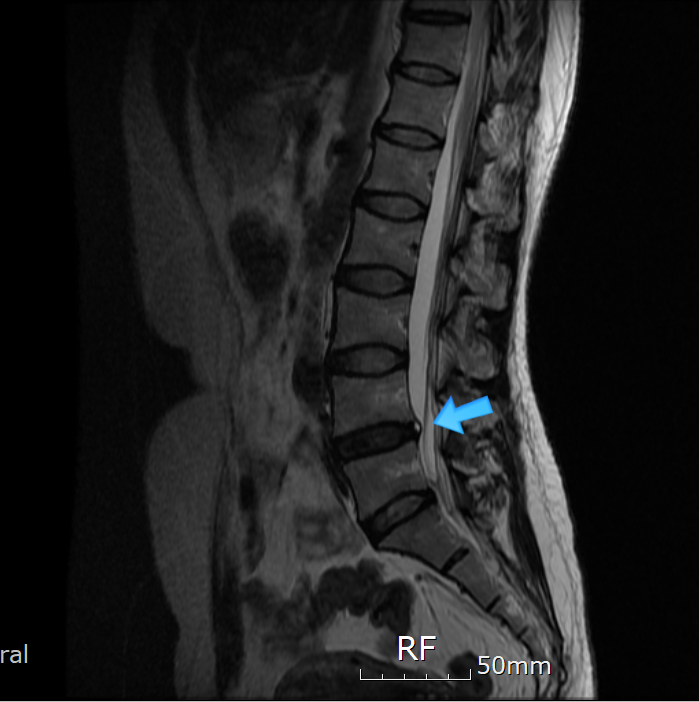

섬유륜파열은 굴곡, 신전, 측굴등의 관절가동범위를 제한하는 극심한 허리통증을 주증상으로 하지만 근력 약화, 하지의 방사통 또는 저리는 감각이 생길수도 있습니다. 허리에 부하되는 작은 압력도 잘 견디지 못하여 milgram test나 balsalva test 등에서 양성이 나오는 경우가 많으며 브릿지 동작등도 하기 힘들어 합니다. 특징적인 임상증상과 경과에 따라 진단하며, MRI 검사가 반드시 권고되는 것은 아니나 MRI 검사상에서 Annulus fibrosus의 열상(tear 또는 fissure)은 T2 강조영상과 조영증강영상에서 고신호강도(high siganl intensity zone)을 보입니다.

섬유륜파열 MRI 소견